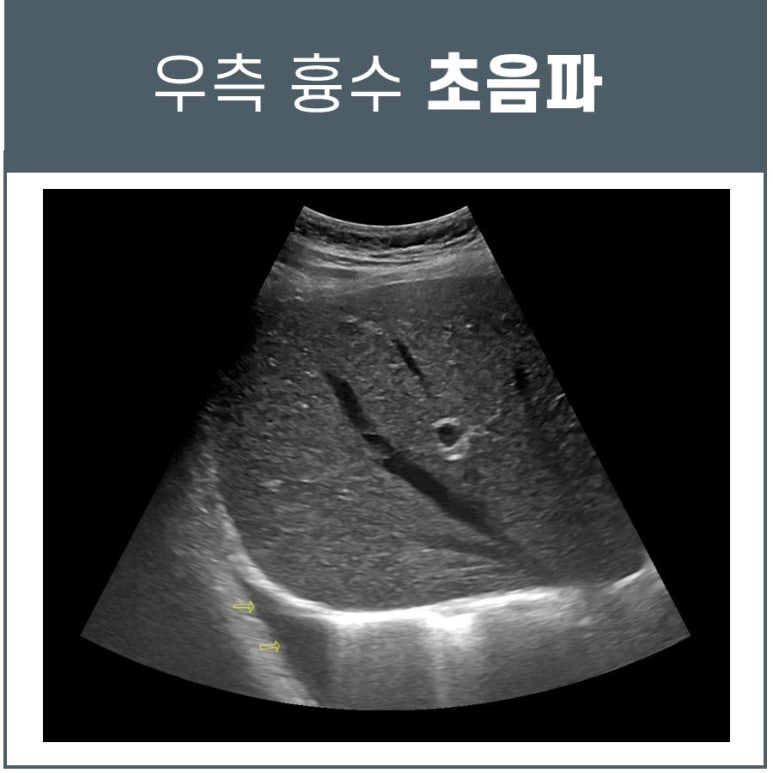

결핵성 늑막염 증상, 단순 근육통이 아닐 수 있습니다

​ 과연 단순 근육통일까? 결핵성 늑막염 증상 최근 헬스 운동 후에 발열, 근육통, 호흡시 우측 옆구리 통증으로 오신 환자분입니다. 운동 후에 담이 결린 것 같다고 스트레칭으로 풀어주니 좀 괜찮다고 하셨는데요.​발열이 있어 코로나 자가키트로 검사해보니 음성으로 나왔고 한의원에서 체온 측정을 해보니 정상으로 나옵니다. ​꼼꼼하게 진료해보니 전형적인 늑막염 증